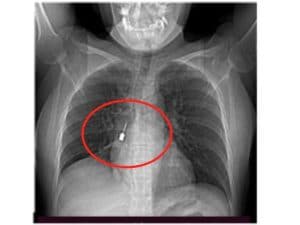

Al pronto soccorso con tosse e dolore toracico, aveva cacciavite odontoiatrico incastrato in un bronco

Il caso di una donna giunta al pronto soccorso del Grande Ospedale Metropolitano di Reggio Calabria e operata d’urgenza per rimuovere il corpo estraneo. Si trattava di un piccolissimo cacciavite odontoiatrico che in qualche modo era stato accidentalmente inalato. Continua a leggere